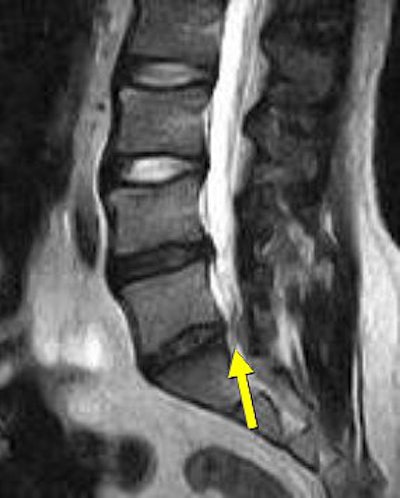

![]() |

| Above, preaxial loaded. Below, axial-loaded image. Central subligamentous disk herniation and discogenic disease at L5-S1 impressing the thecal sac only after axial loading is applied. L4-L5 bulging, discogenic disease, and a central subligamentous disk herniation impressing on the thecal sac. Bulging and discogenic disease at all other levels. |